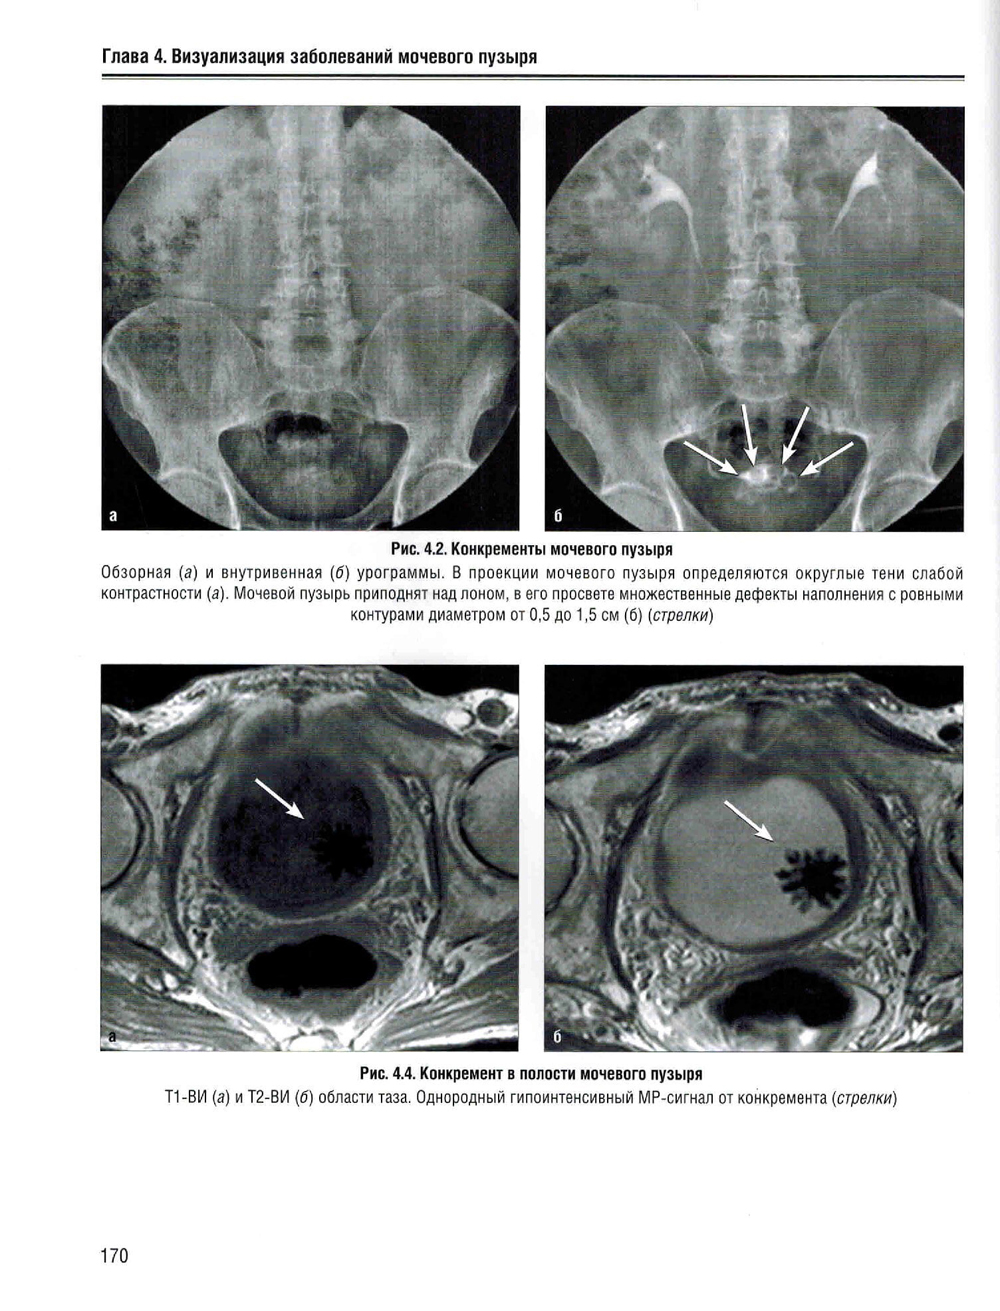

В учебном пособии изложена нормальная лучевая анатомия почек, мочеточников и мочевого пузыря по данным рентгенологического исследования, КТ, МРТ и УЗИ. Приведено описание лучевой семиотики наиболее часто встречающихся заболеваний и повреждений почек, мочеточников и мочевого пузыря с представлением данных УЗИ, КТ и МРТ. Даются рекомендации по тактике лучевого исследования, приводится дифференциальная диагностика. Рассматриваются вопросы этиологии, патогенеза, морфологии и клинические проявления заболеваний. Предназначено для ординаторов, обучающихся по специальностям: 31.08.08 - «Радиология»; 31.08.09 - «Рентгенология»; 31.08.11 - «Ультразвуковая диагностика», а также врачей смежных специальностей. Учебное пособие может быть рекомендовано для подготовки в системе непрерывного медицинского образования.| Издательство | Элби |